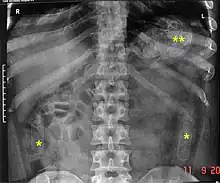

Abdominal X-ray showing swallowed packages of cocaine.

Routine detection of the smuggled packets is extremely difficult, and many cases come to light because a packet has ruptured or because of intestinal obstruction. Unruptured packets may sometimes be detected by rectal or vaginal examination, but the only reliable way is by X-ray of the abdomen. Hashish appears denser than stool, cocaine is approximately the same density as stool, while heroin looks like air.[11][12]